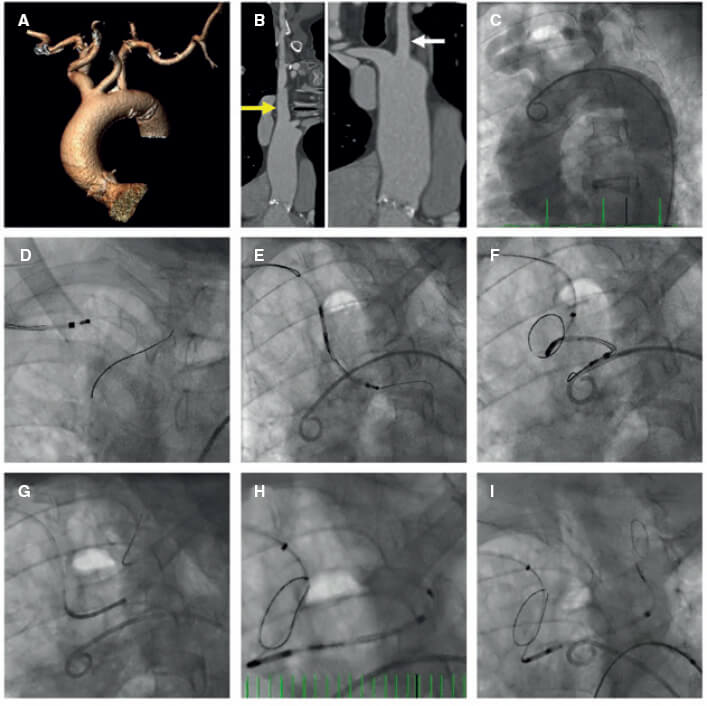

Una mujer de 84 años con estenosis aórtica grave y antecedentes de accidente cerebrovascular no discapacitante fue derivada para implante transcatéter de prótesis valvular aórtica (TAVI). La tomografía computarizada tridimensional realizada confirmó la presencia de un arco aórtico tipo 9 con acentuada tortuosidad (figura 1A). Se optó por proteger las ramas supraaórticas que presentaban diámetros apropiados para poder emplear el sistema de protección embolica cerebral Sentinel (Boston Scientific, Estados Unidos). La longitud de manipulación en la arteria carótida común izquierda (ACCI) fue de al menos 8 cm, que es la distancia entre el filtro proximal y el extremo distal del Sentinel. Figura 1B: flecha amarilla: tronco braquiocefálico, diámetro de 12 mm. Flecha blanca: ACCI, diámetro de 7 mm. Este dispositivo de protección cerebral (DPC) tiene un filtro proximal para diámetros del tronco braquiocefálico de entre 9,0 y 15 mm y un filtro distal para diámetros de la ACCI de entre 6,5 y 10 mm. La angiografía del arco aórtico se muestra en la figura 1C. Se intentó avanzar esta cesta con sistema de doble filtro sobre una guía de 0,014 pulgadas, sin éxito a pesar del uso de una vaina articulada (figura 1D-F). Tras varios intentos, se empleó un catéter multipropósito para llegar a la ACCI (figura 1G). Con ayuda de una guía de 0,014 pulgadas de 300 cm, se intercambió el catéter multipropósito por el DPC lo que permitió su correcto implantante (figura 1H-I). Después de realizar con éxito el TAVI, se procedió a recuperar el DCP vídeo 1 del material adicional). Se obtuvo el consentimiento informado de la paciente.

Figura 1.

En este caso la principal preocupación es cómo compensar el riesgo de accidente cerebrovascular post-TAVI con el riesgo de manipular guías/catéteres en las arterias supraaórticas. Por eso el estudio riguroso con tomografía computarizada es clave para planificar la estrategia a seguir. Presentamos un abordaje alternativo para el implante del dispositivo Sentinel por medio de un catéter multipropósito en un arco aórtico complejo.